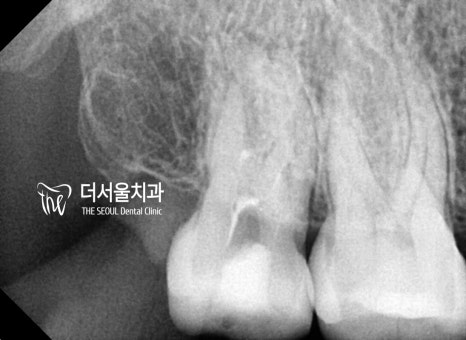

■ 근관 측정 및 청소

우선 감염된 근관 길이를 측정한 뒤

꼼꼼하게 청소를 도왔습니다.

남아있는 세균, 병소 등이 없게끔

눈에 잘 띄지 않는 곳들도 꼼꼼히 확인해야 되는데요.

■ 근관 충전

텅 비어진 근관 내부를

충전재를 이용하여 꽉꽉

채워넣어야 되는데요.

신경치료의 결과를 좌우할 수 있는

중요한 과정이기 때문에

충전재 밀폐까지 확실하게 도와야 됩니다.